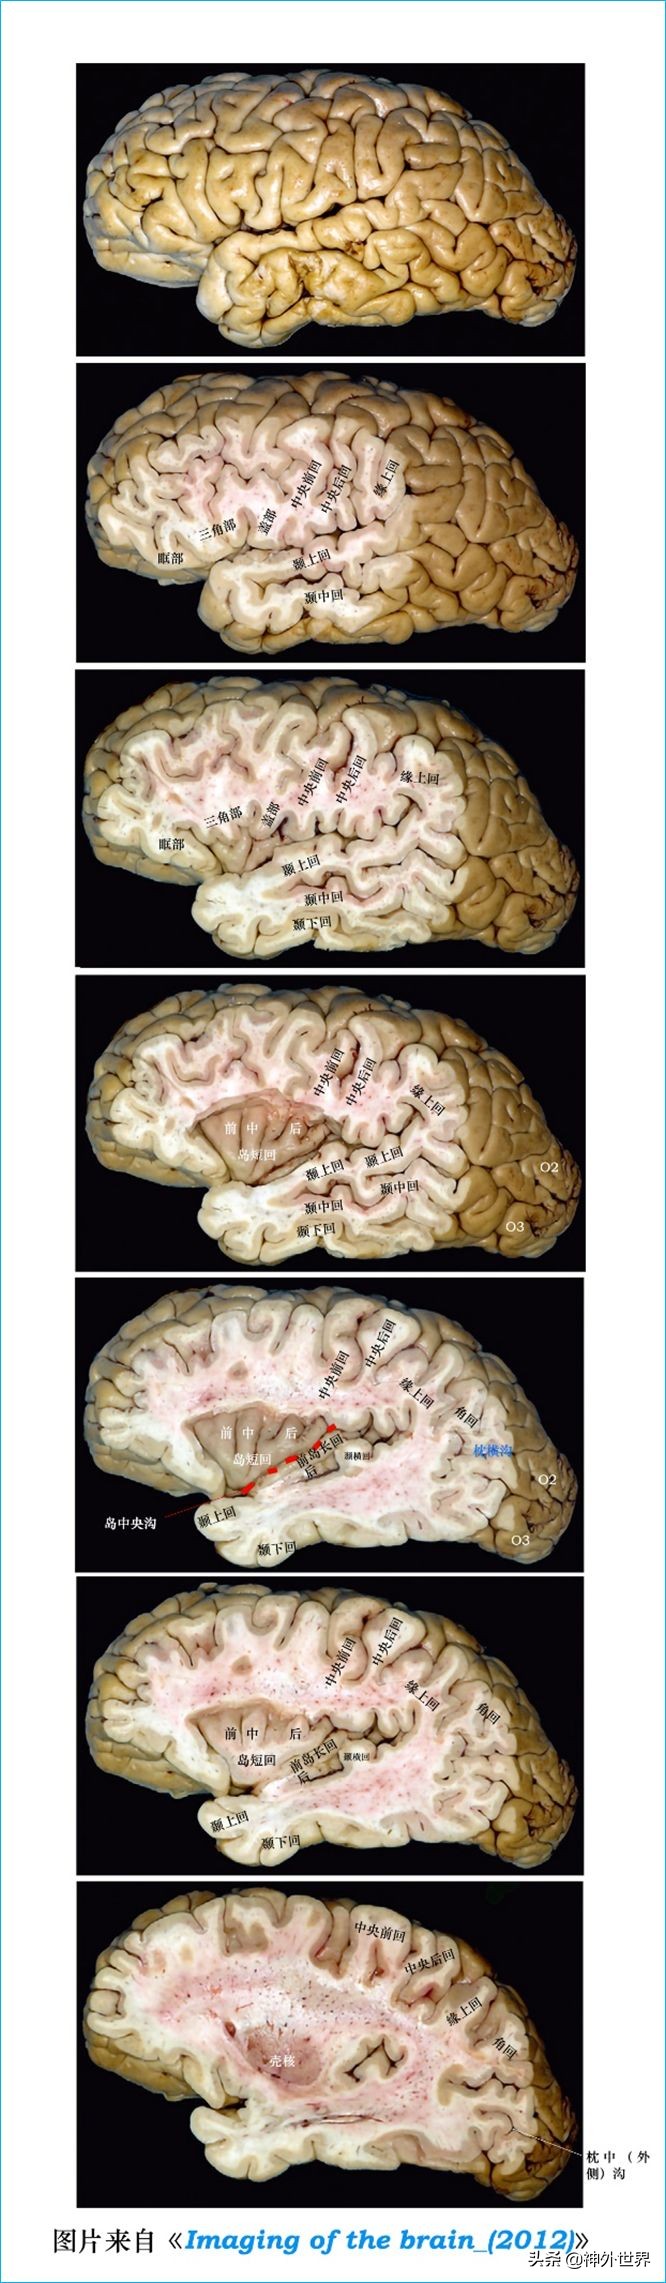

2、大脑半球背外侧面脑沟回定位:

可首先识别外侧裂,然后根据各脑沟回形状与外侧裂的相互关系来定位特定的脑沟脑回。

①确定外侧裂(sylvian fissure)的5个主要分支。

- 典型侧裂的长斜线实际上被称为侧裂的后水平支(posterior horizontal ramus)。

- 在外侧裂的前端,外侧裂的前水平支(anterior horizontal ramus)和前升支(anteriorascending ramus)呈大写字母V或Y的形状,上升到额叶。

- 在侧裂的后端,分叉成后升支和后降支(posterior ascending and posterior descending rami),分别伸入顶叶和颞叶。

- 在外侧裂的上表面,有两个小分支,即下中央前支(anterior subcentral ramus)和下中央后支(posteriorsubcentral ramus)。

- 在外侧裂的下表面,有几个颞横沟(transverse temporal sulci)划定了Hechl‘s颞横回的后缘(posterior margin of the transverse temporal gyrus of Heschl)。识别侧裂臂(arms of the sylvian fissure)建立了参照系和侧面各部分之间的比例。

②三角回征(Triangular gyrussign)。

- 额叶下回呈三角形,正式命名为三角回(triangular gyrus)。这种形状与其他额叶回的纵向和垂直形状完全不同,有助于识别额叶下回。

③M形标志(M sign)。

- 前水平和前升支的V或Y切入额下回三角部,形成字母M的形状。从前到后,M的三个部分是与额叶下表面的眶回相邻的眶部、中间的三角部和作为额盖的盖部。小三角沟(small triangular sulcus)通常在三角部(parstriangularis)形成凹槽。一个小的斜沟,通常在盖部形成凹槽。

2、矢状位连续切片